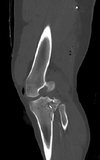

Which of the following conditions is a relative CONTRAINDICATION for use of the flap in the image shown for reconstruction of an 8 x 10-cm anterior ankle wound?

The correct response is Option D.

Hypertension does not preclude the use of any fasciocutaneous flaps in the lower extremity.

Diabetes mellitus can be associated with peripheral vascular disease, but by itself, would not prevent successful use of the reverse sural artery flap for foot or ankle reconstruction. Appropriate preoperative workup would include noninvasive ultrasound study of the lower extremity vasculature to prove the peroneal artery was patent.

Vascularized flaps, including the reverse sural artery flap, provide excellent coverage for foot/ankle wounds, including those with underlying osteomyelitis. Effective treatment would necessitate adequate debridement and antibiotic therapy as part of the reconstructive paradigm.

The distally based sural artery flap receives its blood supply from a few sources, the most robust of which are perforators from the peroneal artery. The most distal of these perforators arise between 4 and 7 cm proximal to the lateral malleolus. Additional perfusion arises from neurocutaneous perforators from the sural nerve and venocutaneous perforators from the lesser saphenous vein.